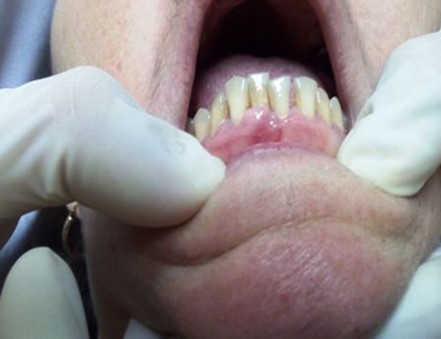

Volver a los detalles del artículo Hiperplasia gingival inducida por amlodipino en paciente con periodontitis crónica. Presentación de un caso